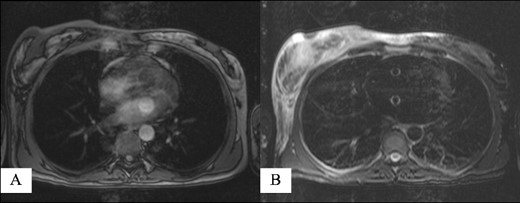

Due to the above findings, computed tomography (CT) (Fig. 3) and magnetic resonance imaging (MRI) were obtained. An MRI reported an area of 9.6 × 5 × 7.3 mm in the right breast enhanced by contrast uptake. The process infiltrated a segment of the overlying skin, and the MRI was labeled as Breast Imaging Reporting and Data System (BIRADS) category 4C (Fig. 4); therefore, a biopsy was requested.

Magnetic resonance imaging reporting an area of 9.6 × 5 × 7.3 mm in the right breast enhanced by contrast uptake: (A) T1-weighted sequence and (B) T2-weighted sequence.